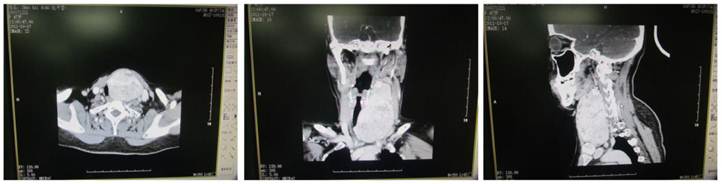

Figure 4

CT of retrosternal giant nodular goiter. The oval mass was found between the left neck and the Tracheal bifurcation and had clear border but uneven density. Uneven enhancement was noted. The surrounding tissues were compressed and the trachea was pushed toward the right side.

Plain CT scan showed the lesion was focal and enhancement CT scan revealed enhancement of different extents. There were 46 patients with esophageal compression and 25 had tracheal compression (Figure 3). Cervical X ray can reveal the tracheal compression, dislocation or stenosis. Positive lateral X ray can reveal the degree of tracheal compression. The difference in tracheal diameter between inspiration and expiration of >5 mm can be used to diagnose tracheomalacia. Retrosternal giant goiter was manifested by mass with different densities in the mediastinal region, and enhancement CT showed uneven enhancement accompanied by compression of adjacent organs (Figure 4).